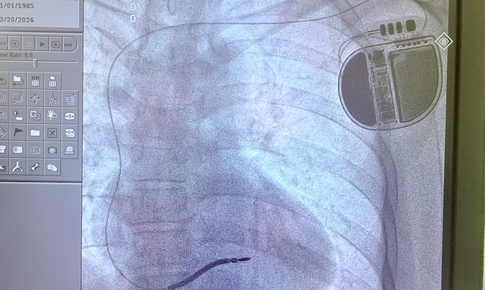

máy khử rung tim tự động

Khởi động trang bị máy khử rung tim tự động cho cộng đồng đầu tiên tại Việt Nam

Tin nóng y tế - 19/09/2025 17:11SKĐS - Việc triển khai dự án máy khử rung tim tự động cho cộng đồng nhằm hướng tới hai mục tiêu bổ sung trang thiết bị sơ cứu và nâng cao nhận thức, kỹ năng, từ đó nâng cao hiệu quả cấp cứu ban đầu tại cộng đồng, đặc biệt trong các tình huống ngừng tuần hoàn xảy ra ngoài cơ sở y tế.